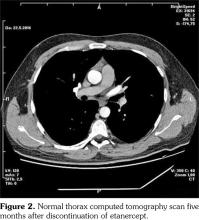

Lymph node biopsy was performed by broncoscopy and endobronchial ultrasonography. Biopsy result was compatible with granulomatous disease. All the infectious studies performed on pulmonary lymph node tissues were negative. Angiotensin converting enzyme level was at the upper limit with a value of 47.6 U/L (normal: 8-52 U/L). Sarcoidosis was found to be compatible with the condition after excluding tuberculosis. Etanercept was ceased following the diagnosis of sarcoidosis. No additional medical treatment was suggested for sarcoidosis. Non- steroid anti-inflammatory drugs were prescribed for the control of AS. Five months later, follow- up thorax computed tomography scan showed resolution of the mediastinal lymphadenopathies (Figure 2).